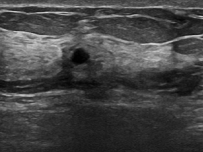

4.1.4 Ultrasound breast cancer

Breast cancer has gained significant attention in recent times due to its high mortality rate and the increasing number of reported cases. Using the ultrasound imaging technique makes it possible to observe the tissue distribution for cancer visual detection, making it an early detection alternative to diminish the public health impact. The dataset444https://www.kaggle.com/datasets/sabahesaraki/breast-ultrasound-images-dataset used in this work contains 780 images with three categories: benign with 442 images, malignant with 206, and normal with 132. The scans were collected from 600 women between 25 and 75 years old. It is a highly unbalanced dataset with different image sizes, having an average of pixels. Figure 5 showcases examples from each of the three described classes.